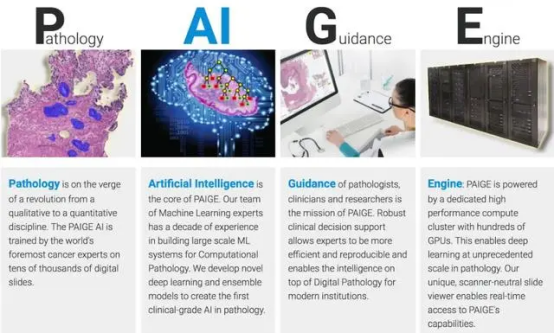

类似的例子,还有用AI技术帮助医生分析癌症病理图像,以及发现新的治疗方法和药物的Paige.AI。

Paige原本利用自有50万份癌症医学病理学切片的10亿张图片,创建全球第一个大型基础模型。在和微软合作下,双方将开发全球规模最大的癌症图片AI模型,参数高达十亿。